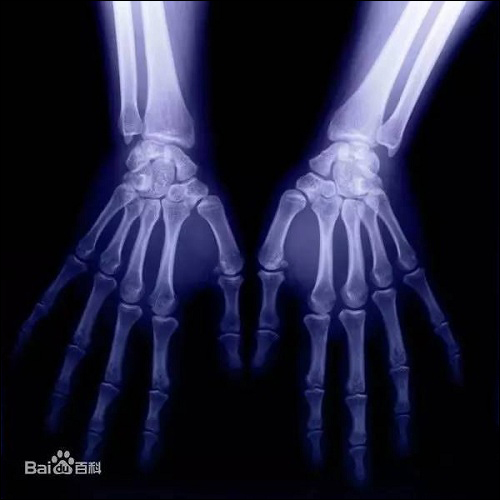

x射线的发现纯属是一个偶然的机会,1895年11月8日傍晚,伦琴在实验室研究阴极射线,实验完成切断电源后,却意外地发现一米以外的一个小工作台上有闪光,而且可以穿透肌肉照出手骨轮廓,于是他请夫人把手放在用黑纸包严的照相底片上,然后用X射线对准照射15分钟,显影后底片上清晰地呈现出夫人的手骨像,手指上的结婚戒指也很清楚。人类历史上第一张X光片就此诞生。

伦琴发现X射线使X射线研究迅速升温。几个星期之后,医生开始应用X射线准确地显示人体骨骼,这是物理学的新发现在医学中最迅速的应用。随后,欧洲不少医院创立了用X射线检查食道、肠道和胃的方法,受检查者吞服一种造影剂(如硫酸钡),再经X射线照射,便可显示出病变部位的情景。时至今日,X射线诊断仪一直作为医院中最重要的诊断仪器。